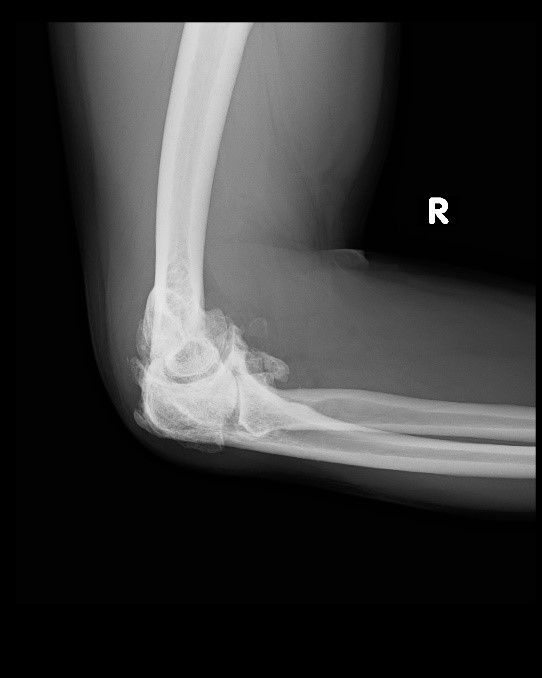

From www.svuhradiology.ie

Rheumatoid arthritis elbow Radiology at St. Vincent's University Elbow Arthritis Medicine Elbow arthritis is degenerative joint disease of the elbow that can be broken into three main types: If your elbow arthritis is due to a form of inflammatory arthritis, like rheumatoid arthritis, your doctor should refer you to a rheumatologist. You can normally treat this pain. Elbow arthritis occurs when the cartilage in the elbow has wear and tear from. Elbow Arthritis Medicine.